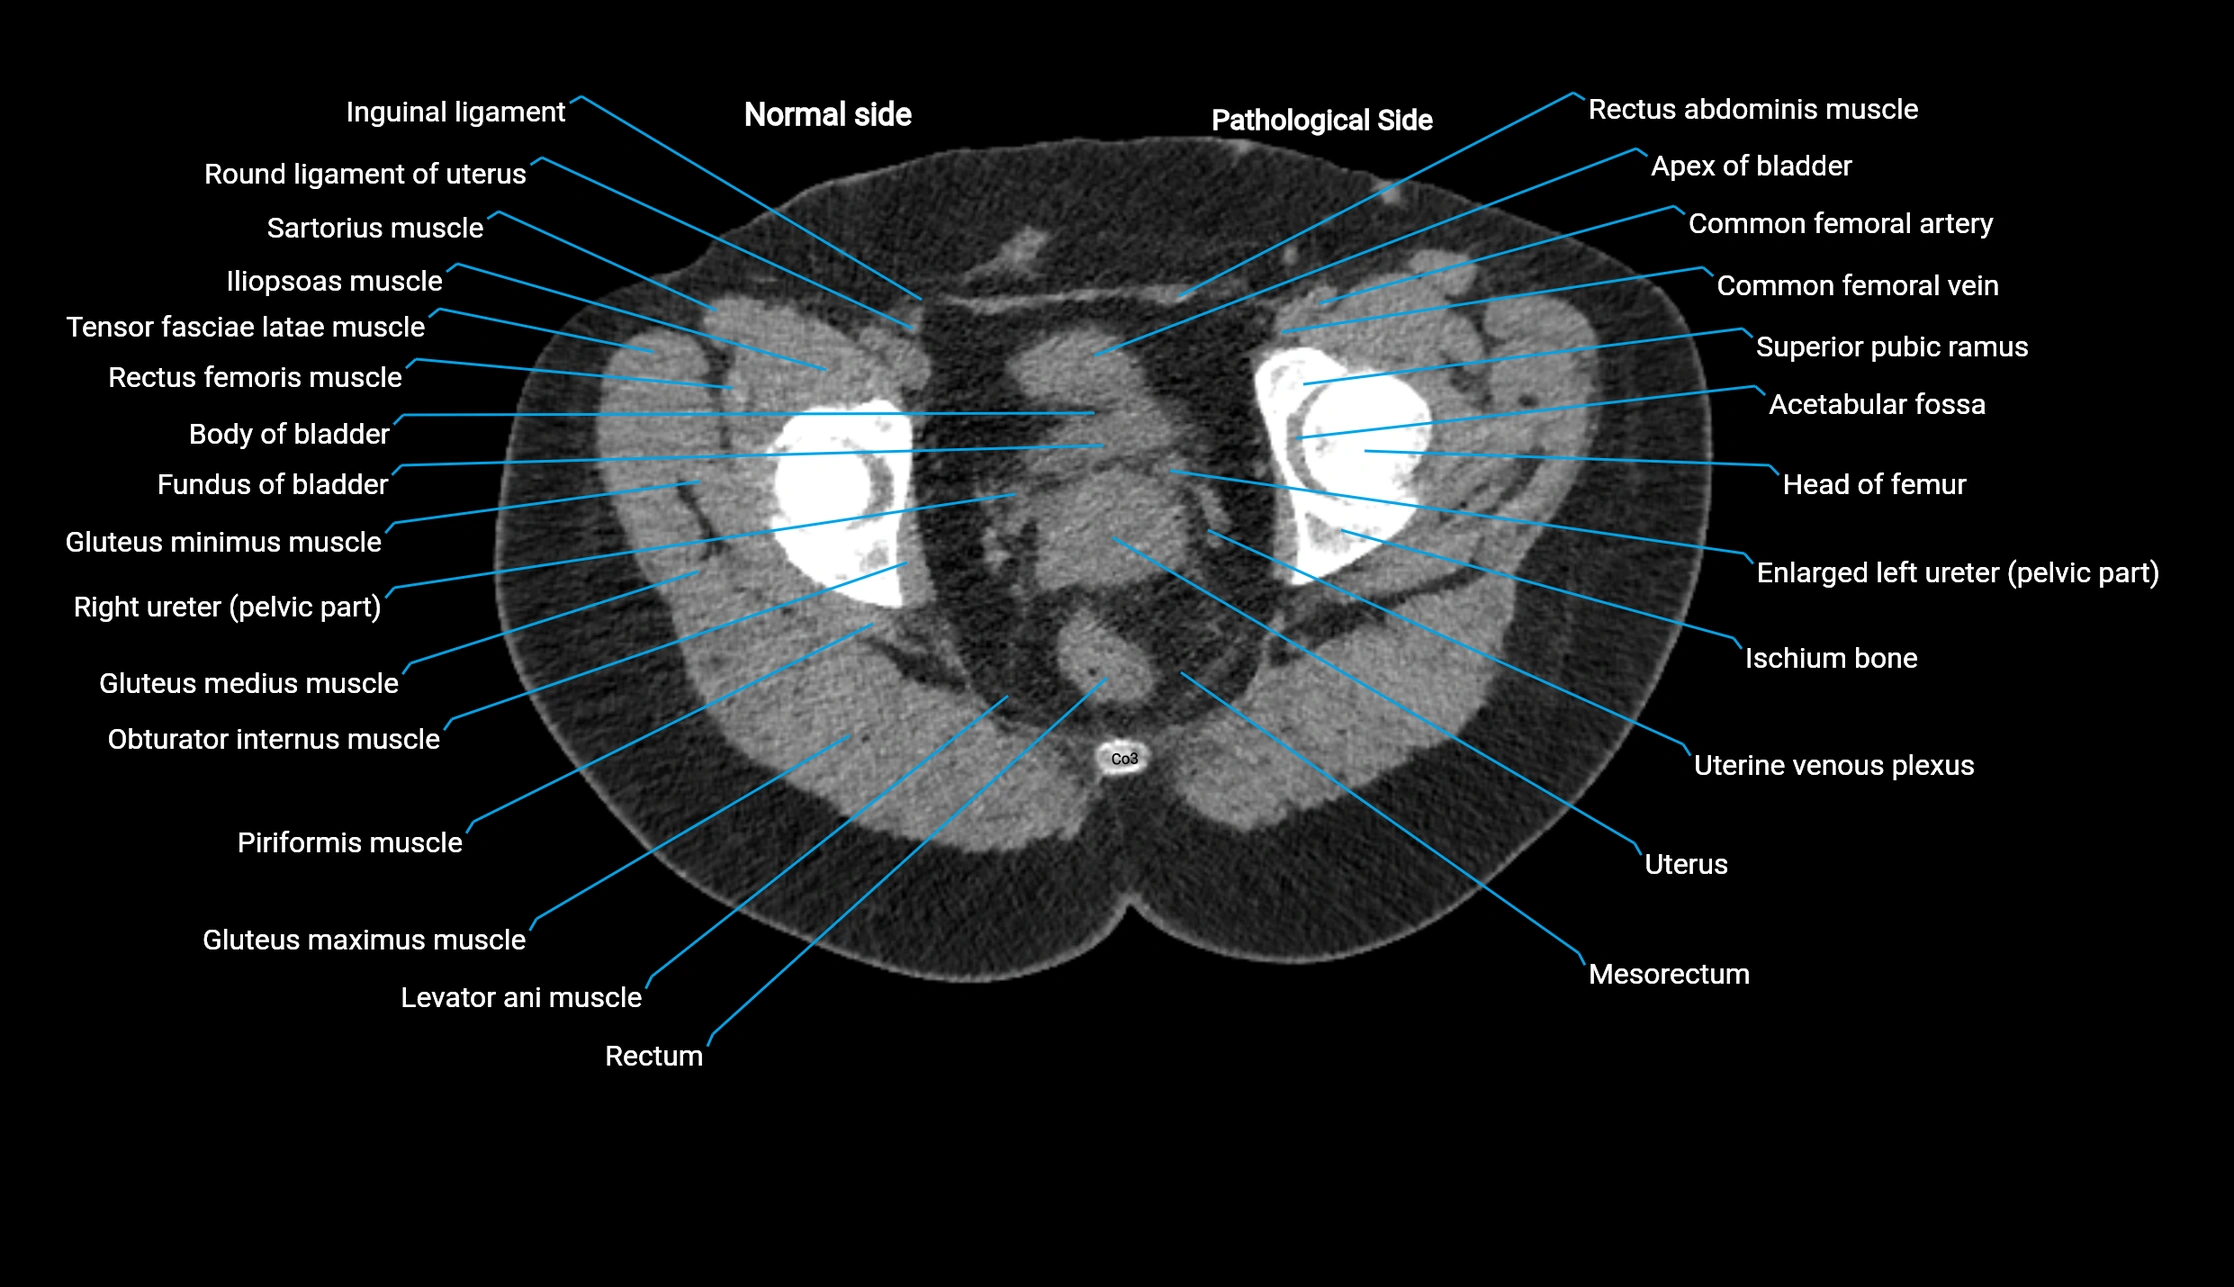

CT image

image